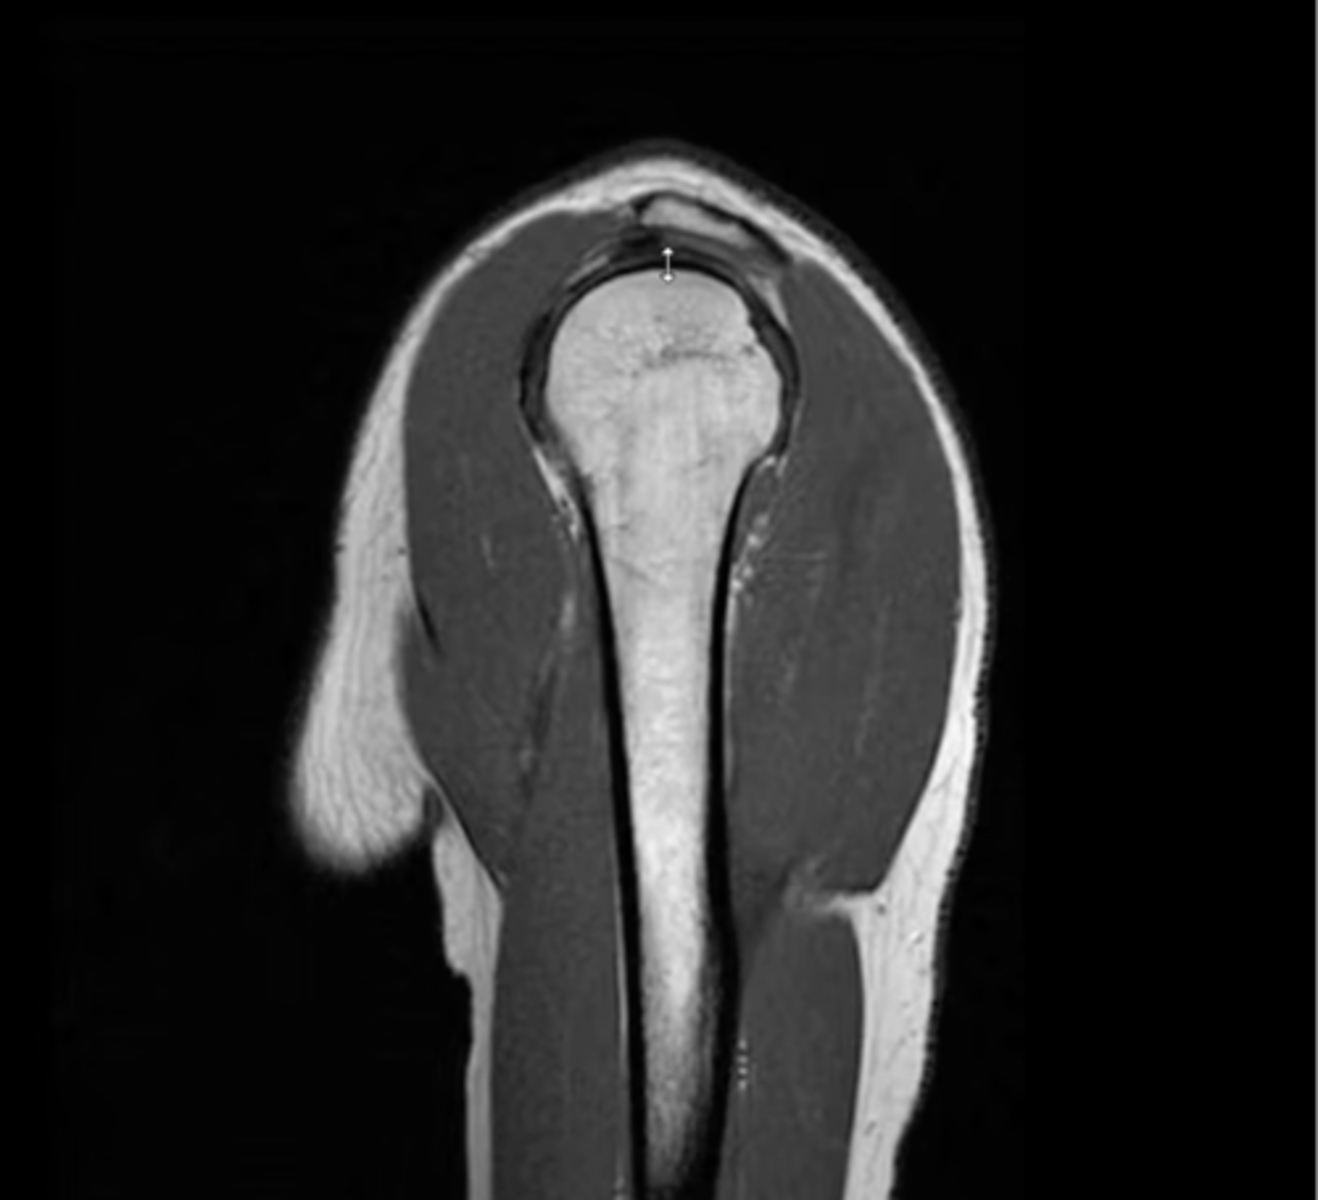

1. Sagittal = slices outside --> in

2. Coronal = slices w/ a traditional AP view

3. Axial = slices looking down

Explain the difference between each of the MRI slices.

Sagittal view of the anterior, middle, and posterior deltoid (from left to right)

What type of view is this?

1. Anterior deltoid

2. Middle deltoid

3. Posterior deltoid

From left to right, which structures are being pointed to?

1. Anterior coronal view

2. Lung space (this is not as easily visualized from a posterior view due to the movement of the scapula on the thorax while laying down)

Note: usually, a great way to tell is by the coracoid process, but it is NOT visible this superficially

1. Which view is this?

2. How do we know -- from what we can see here?